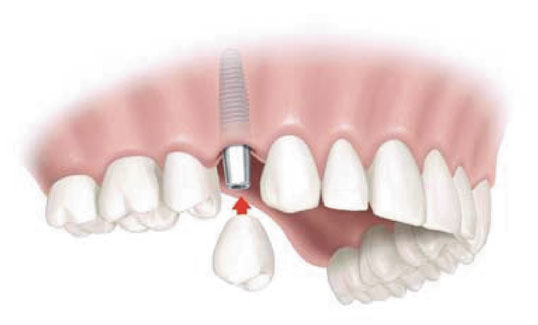

Leczenie implantologiczne to obecnie najskuteczniejsza i najbardziej komfortowa metoda uzupełniania braków zębowych. Implanty stomatologiczne mają postać tytanowych śrub wprowadzonych do kości szczęki lub żuchwy, a których zadaniem jest zastąpienie korzenia brakującego zęba. Na takim fundamencie montuje się koronę protetyczną. Zastosowanie implantów pozwala na uzyskanie zadowalającego efektu estetycznego i funkcjonalnego bez konieczności ingerencji w struktury sąsiednich zębów, jak to ma miejsce przy szlifowaniu zębów pod mosty protetyczne. Ponadto implanty umożliwiają często uniknięcie konieczności użytkowania uzupełnień ruchomych, a stosowane w naszym gabinecie rozwiązania w postaci elementów mocujących na implantach (np. zaczepów kulowych, belek) pozwalają na poprawę stabilizacji protez całkowitych, a których zbyt duża ruchomość w jamie ustnej pacjenta była powodem dyskomfortu.

W gabinecie Dentomedica stosujemy implanty jednoczęściowe i dwuczęściowe, a także przeprowadzamy zabiegi implantacji natychmiastowej bezpośrednio po ekstrakcji zęba lub odroczonej, która ma miejsce po wygojeniu zębodołu. Strategia postępowania jak i dobór odpowiedniego implantu uzależniony jest od uwarunkowań klinicznych. W przypadku odbudowy protetycznej również mamy dwie drogi działania. Możliwa jest ona zaraz po wprowadzeniu wszczepu lub po okresie osteointegracji, czyli „zrośnięcia się” kości z implantem, jednak i ten aspekt należy rozpatrywać indywidualnie.